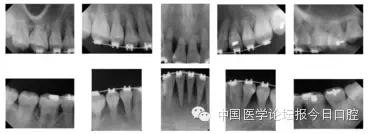

图1为患者初诊的口内相,图2为我们为患者进行检查的牙周记录表,图3为患者的全口根尖X线片,从中我们可以发现几个关键问题:

▲图3 患者初诊的全口根尖片

▲图13 正畸治疗结束后全口根尖片

▲图14 正畸结束后全口牙周检查记录表(全口无超过5mm的牙周袋,探诊出血不明显)